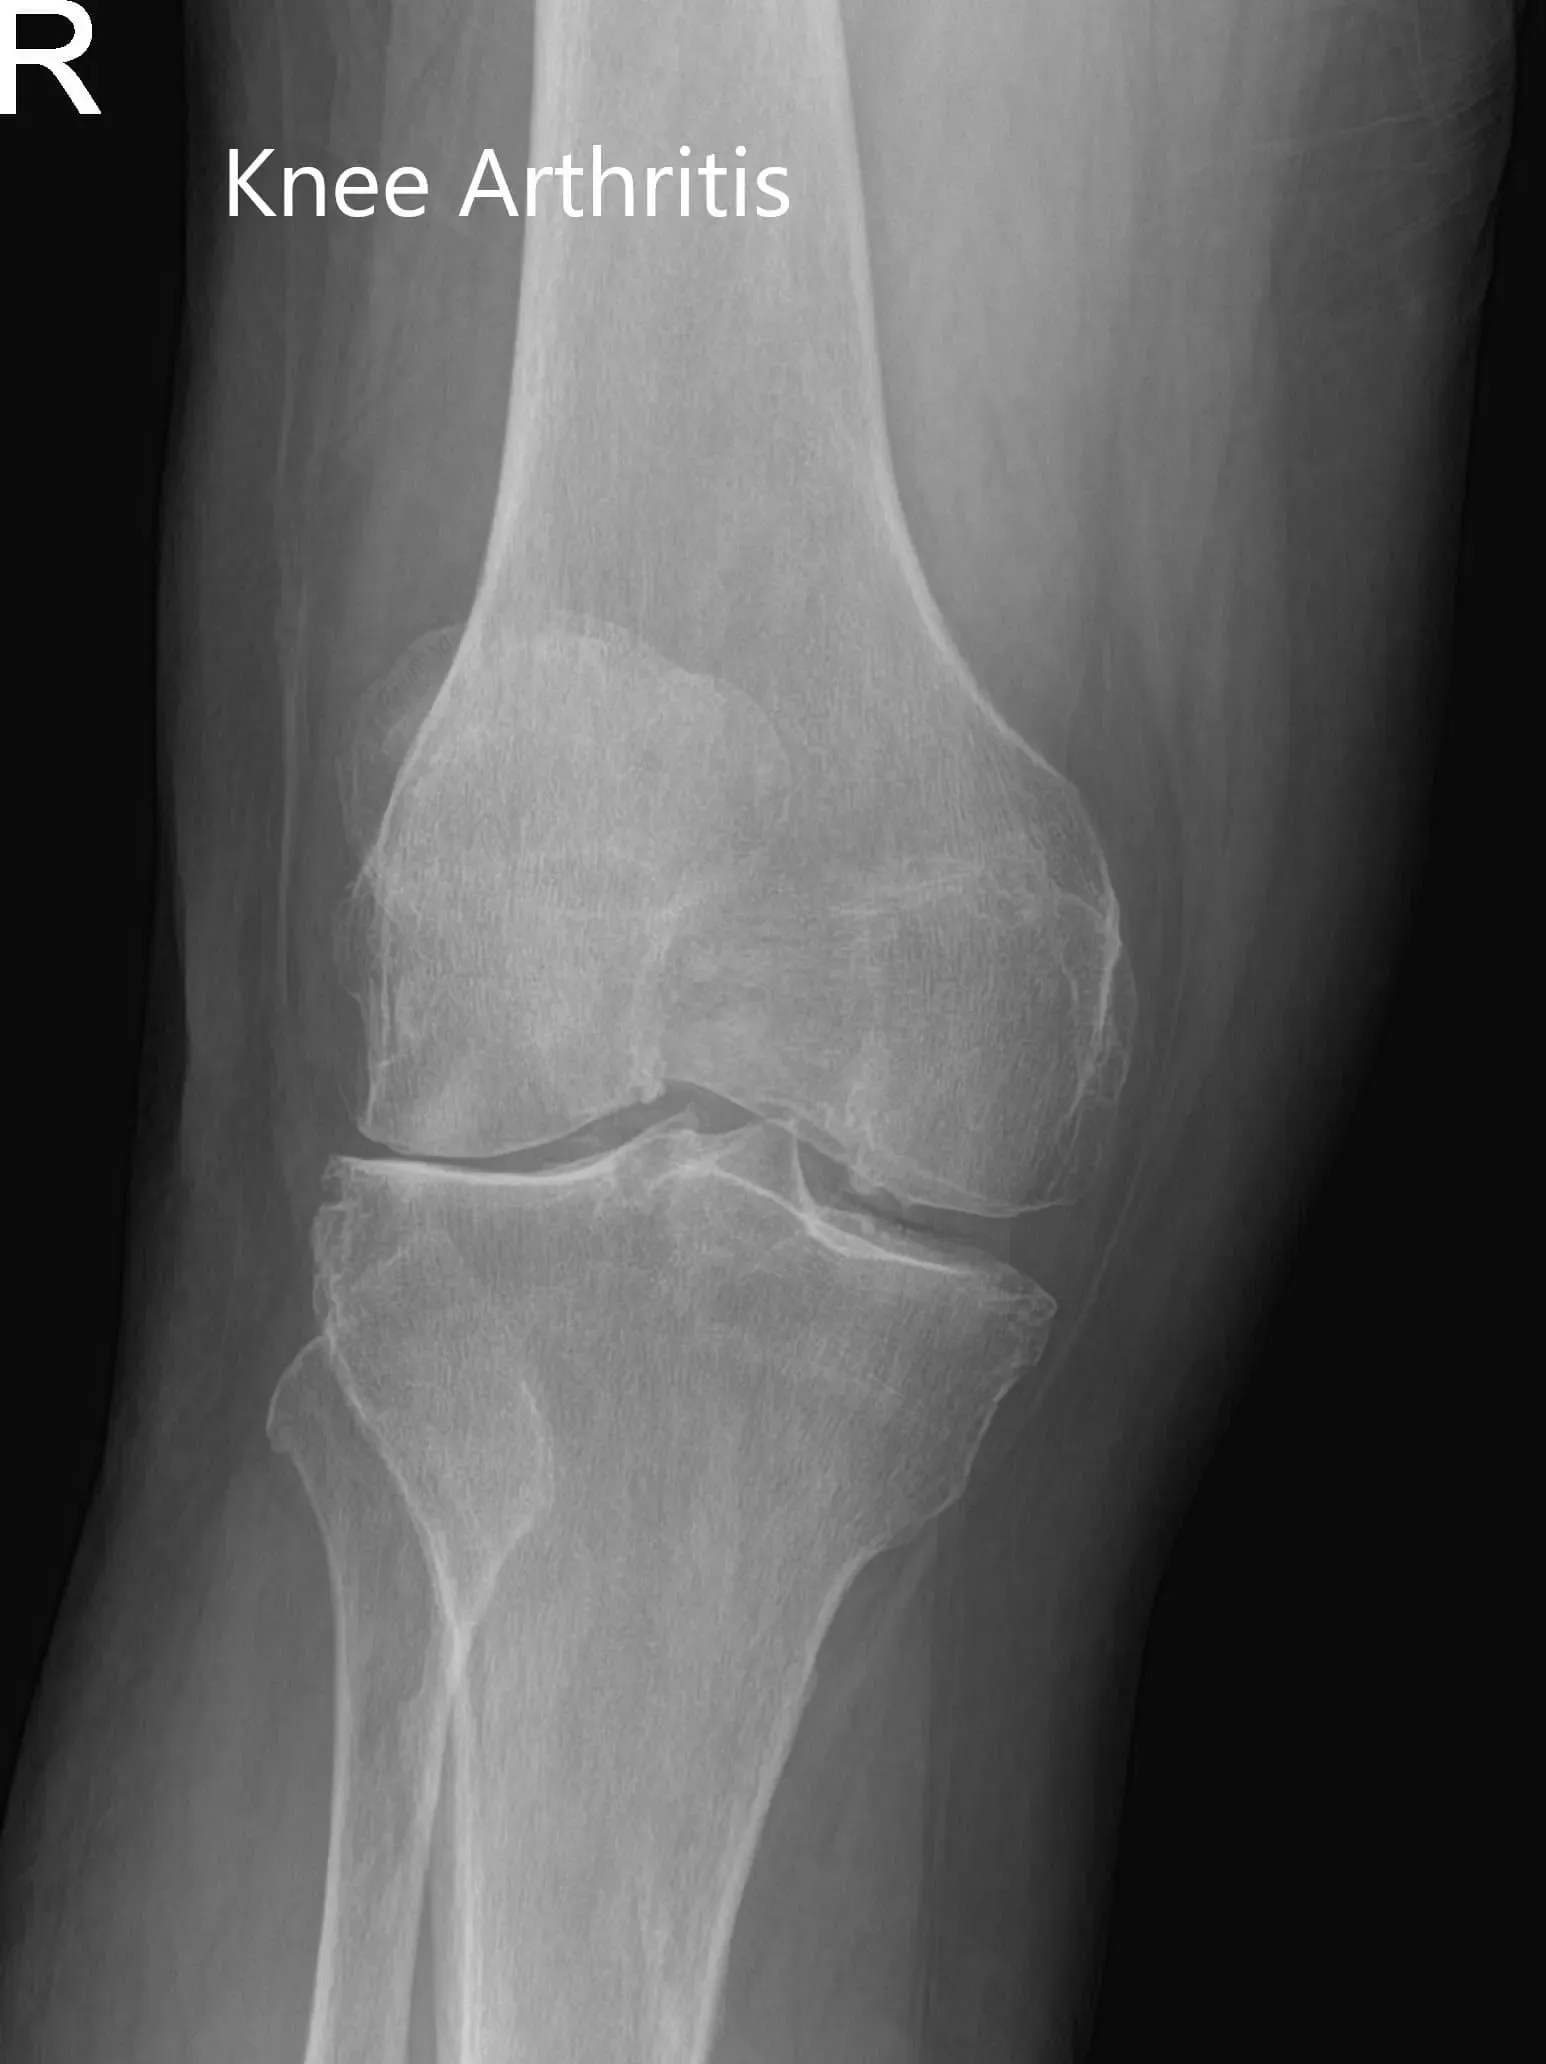

Los estudios de imagen revelaron una artritis bilateral severa de rodilla. La rodilla derecha estaba peor que la izquierda. Le recomendaron un reemplazo total de rodilla con instrumentos personalizados. Se discutieron extensamente con ella riesgos, beneficios y alternativas. Ella estuvo de acuerdo con el plan.

Radiografía de la rodilla derecha en vistas anteroposterior y lateral.